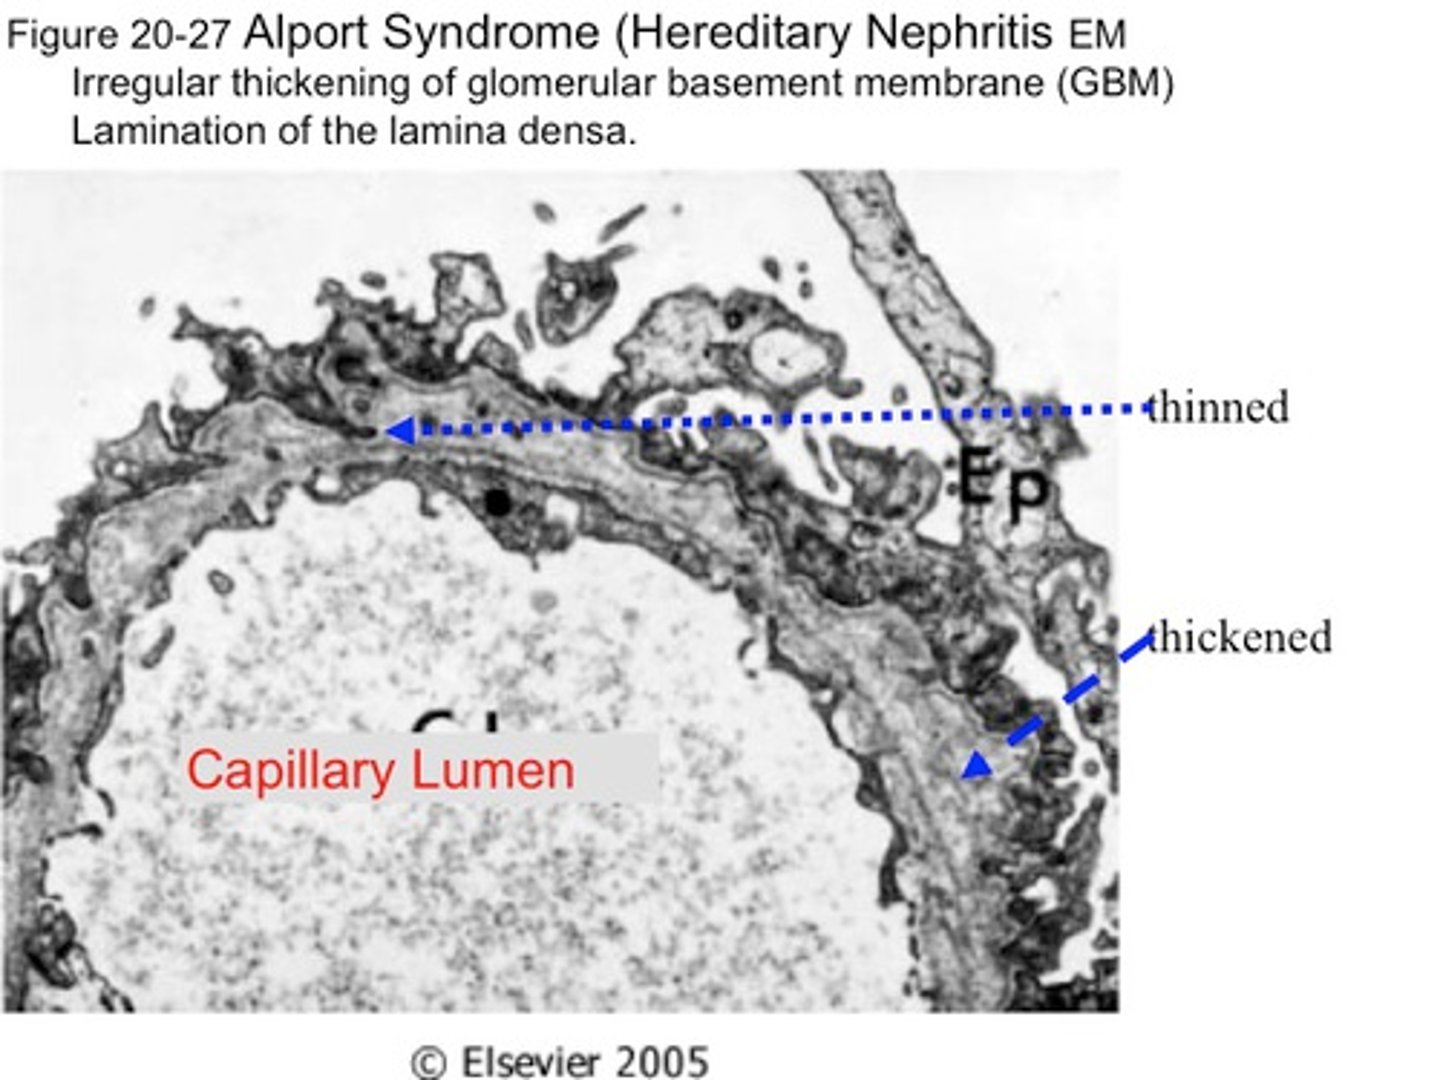

Hereditary nephritis, sensorineural hearing loss, cataracts in boys

Alport syndrome (mutation in collagen IV)

X-linked

Irregular thickening of GBM

Basket Weave (thinning) on EM

Isolated hematuria